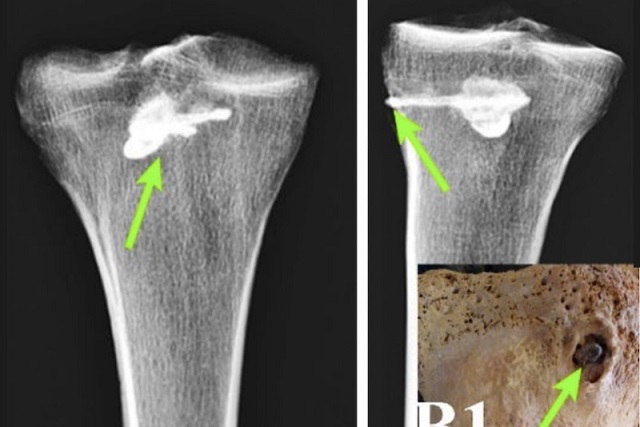

İran’daki mezarlıkta bulunan Part dönemi savaşçısının ok saplanmış kemiği. C: Eghdami, M. R., Roudbordeh, M. G., & Navaeiyan, M. (2025).

İran’ın Gilan bölgesindeki Liyarsangbon Mezarlığı’nda Part dönemine (MÖ 247 – MS 224) ait iskelet kalıntıları üzerinde yapılan yeni bir araştırma, antik savaş ve tıp becerilerine dair önemli bilgiler sunuyor. Bilim insanları, bir bireyin sağ kaval kemiğine (tibia) saplanmış demir bir ok ucunun, dönemin metalurji dehasını ve cerrahi yetersizliğini aynı anda gözler önüne serdiğini belirtiyor.

Araştırmanın odak noktası, iskeletin sağ kaval kemiğine (tibia) derinlemesine saplanmış olan demir ok ucuydu. Kemiğin tahrip edilmemesi amacıyla XRF (X-ışını floresansı) ve Quantometer gibi zarar vermeyen test yöntemleri kullanıldı.

Bilgisayarlı Tomografi (BT) taramaları, kemiğin içinde metalik bir nesnenin varlığını gösteren 4000 Hounsfield birimi değerini ortaya çıkardı.

Paleopatoloji incelemeleri, ok yarasının şiddeti hakkında önemli ipuçları verdi. Ok, kaval kemiğine son derece isabetli bir şekilde saplanmış olmasına rağmen, görüntüleme çalışmaları ok yarasının yakınında tipik kırık veya deformasyon belirtilerinin olmadığını gösterdi. Bu durum, silah kullanımında dikkate değer bir isabet olduğunu kanıtlıyor.

Daha da önemlisi, ok ucunun etrafındaki kemik yapısı, bireyin bu yaralanmadan sonra yaşamaya devam ettiğini gösteren iyileşme işaretleri sergiliyordu. Ok ucunun saplandığı bölgenin etrafındaki kemik dokusu, zamanla yoğunlaşarak kompakt kemiğe dönüşmüştü. Tibia’nın ok ucunun girdiği yer olan tibial tüberozite bölgesinde 11.6 mm çapında yuvarlak, kompakt yeni kemik oluşumu gözlemlendi. Ayrıca, ok ucu çevresinde enfeksiyon belirtisi (yeni kemik büyümesi veya deformite) olmaması, o dönemin tıbbi ve ilaç uygulamaları hakkında kapsamlı bir anlayışa sahip olunabileceğini düşündürüyor.